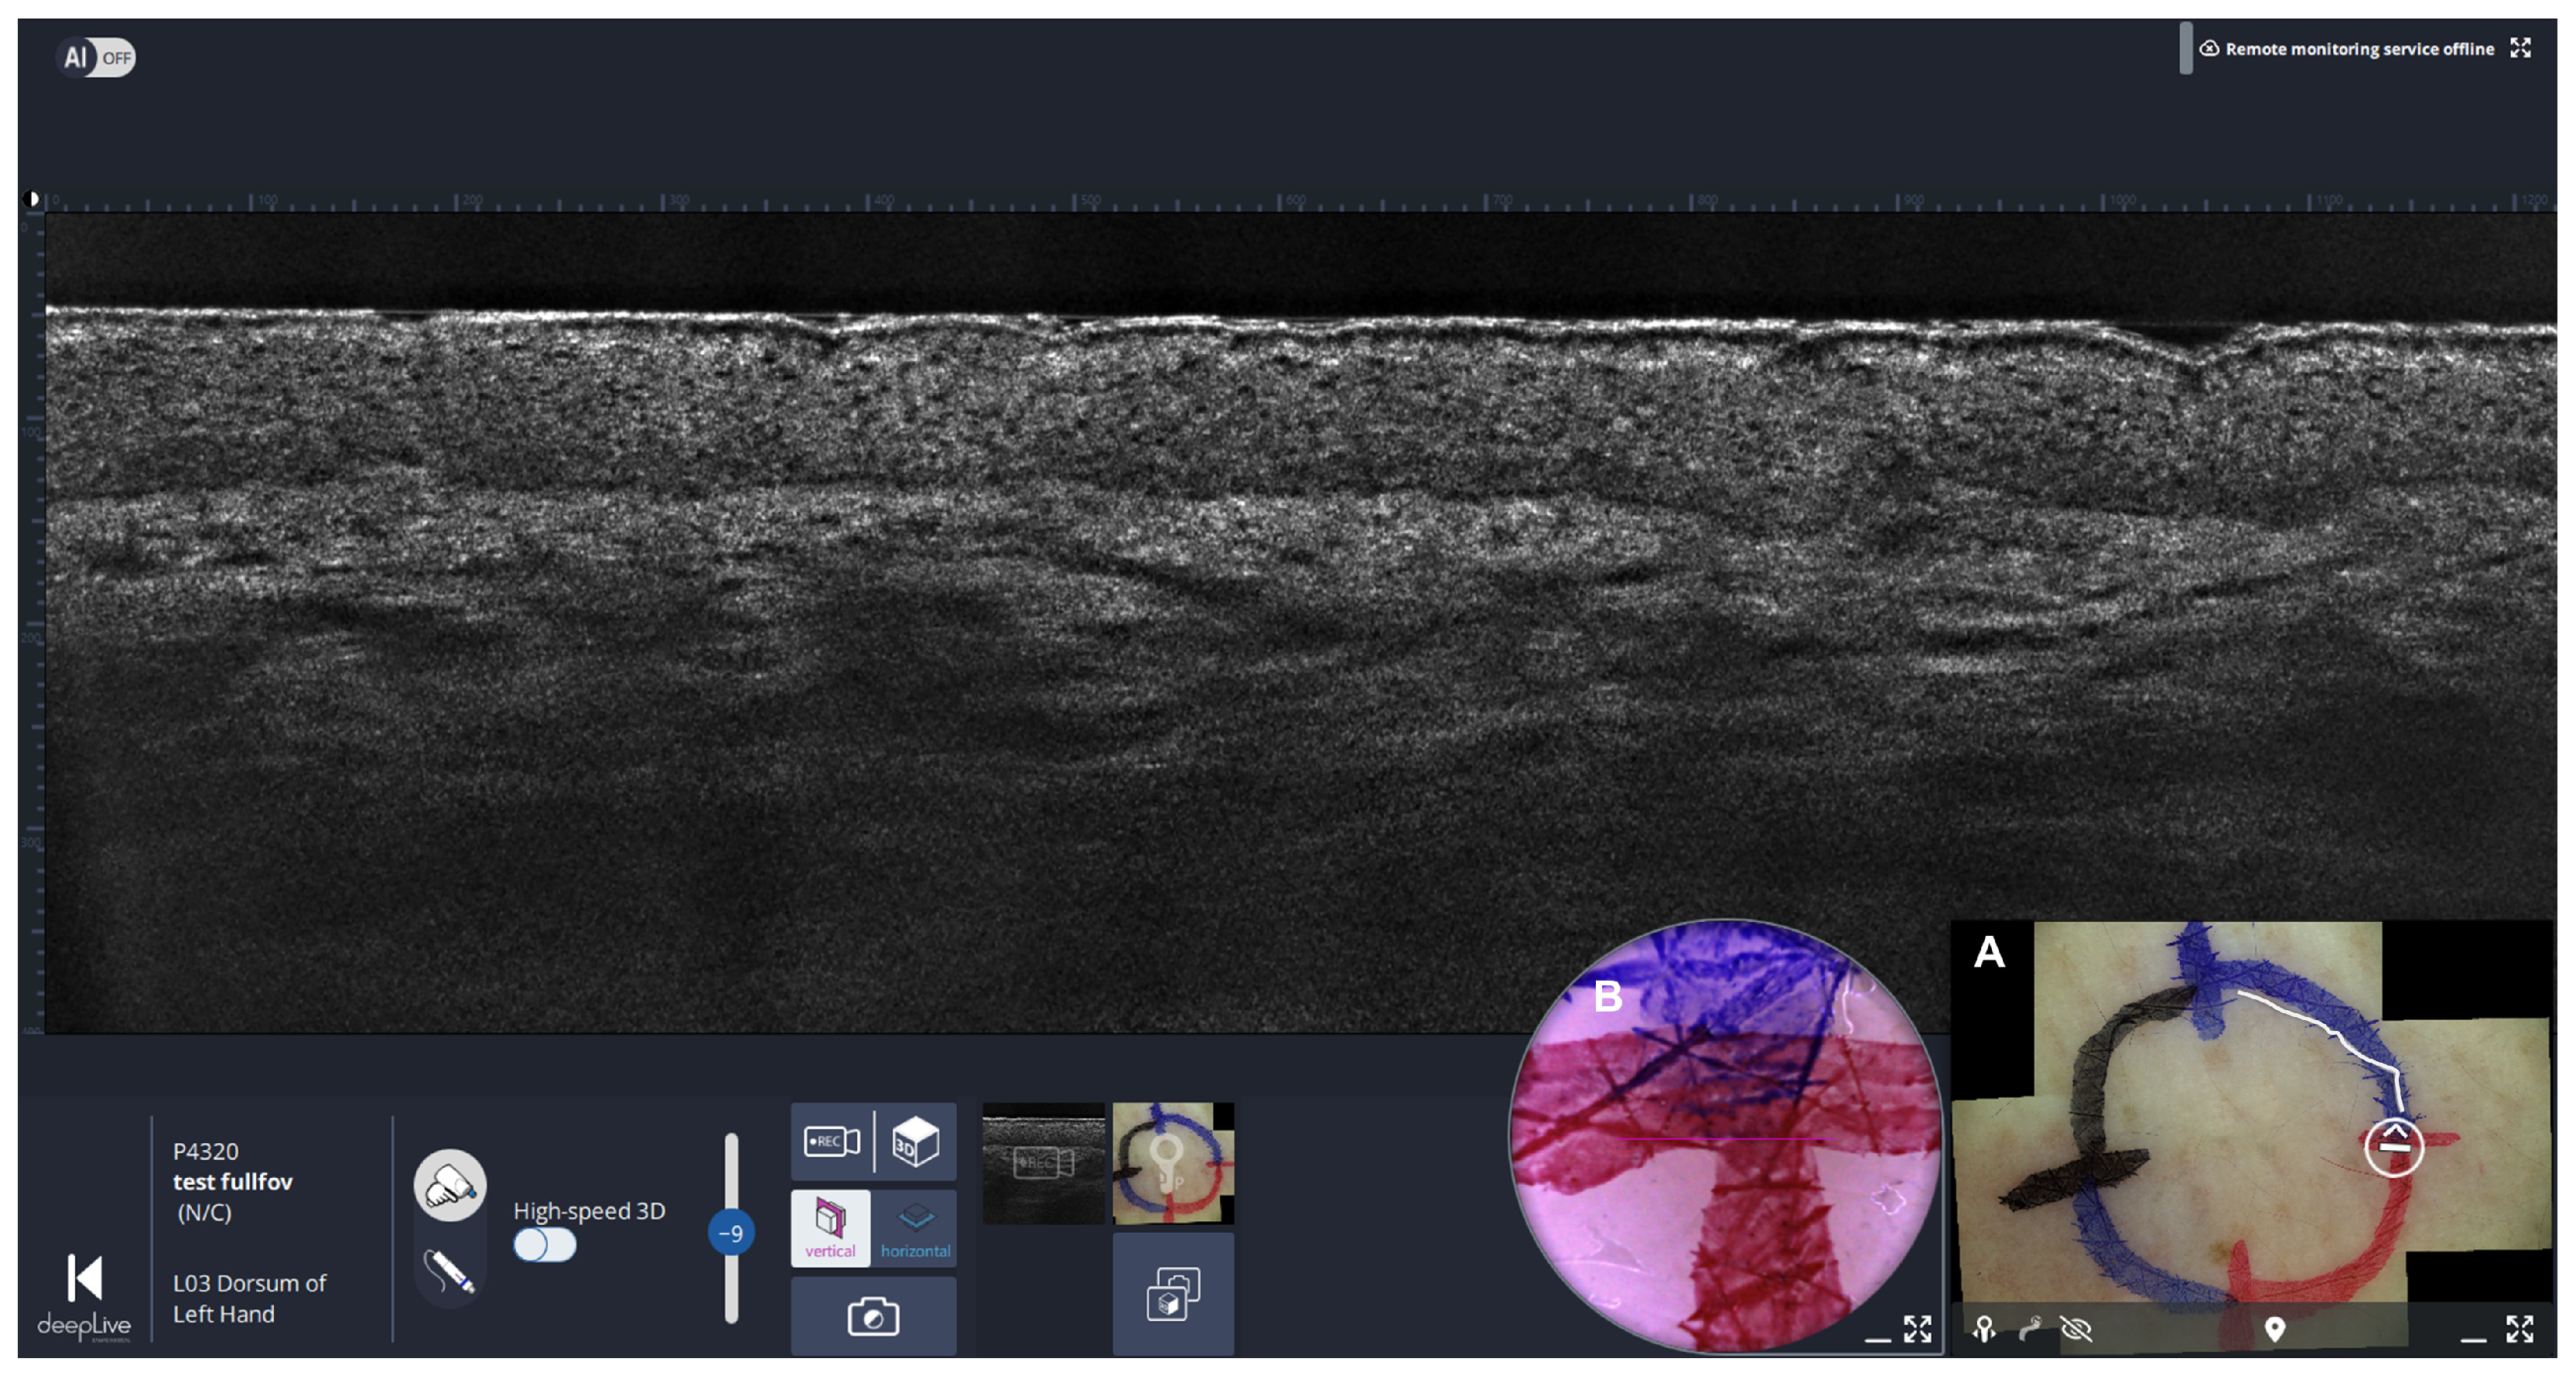

3.1.2. LC-OCT Imaging

3.1.3. Final LC-OCT Review